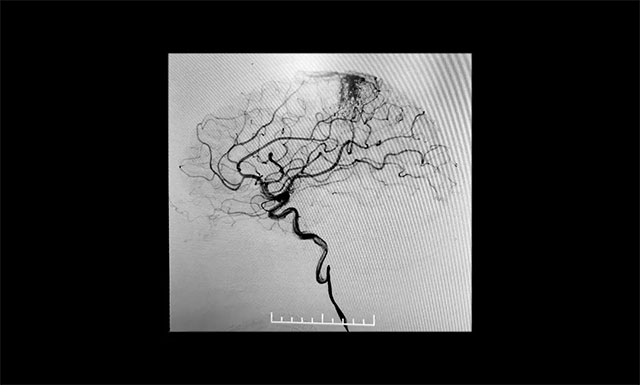

▲ DSA检查显示,中央后回动静脉畸形

患者为55岁男性,4月份突发右眼失明,头颅CT+CTA显示,左侧顶叶异常强化灶,考虑血管畸形AVM可能。经医院DSA检查,确诊为功能区动静脉畸形,畸形团分布较弥散,位于中央后回,主要由大脑前动脉分支供血,通过皮层静脉向上矢状窦引流。该患者畸形血管团体积较大,且与其相连的供血动脉及回流静脉交织纷乱、复杂、异常粗大,病灶紧邻运动中枢、语言中枢、书写中枢等重要结构。